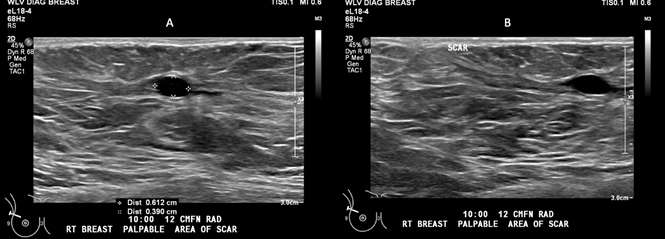

Ultrasound Findings: As with mammography, the ultrasound appearance of fat necrosis is variable and tends to evolve over time. Fat necrosis may appear as a solid, complex cystic and solid, or a cystic/anechoic mass. Complex cystic and solid masses may contain internal echogenicity or mural nodules. Though not always visualized, the presence of shifting positional echogenic bands is relatively specific for fat necrosis.4 When presenting as an anechoic mass/oil cyst, often no posterior acoustic enhancement is present, differing from what would be typical in simple cysts. When intralesional or rim calcifications are present, fat necrosis can be associated with posterior acoustic shadowing, though again the imaging appearance is variable and fat necrosis with posterior acoustic enhancement has also been demonstrated.5